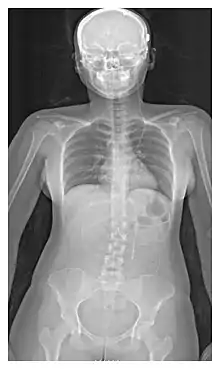

X-ray of a ventriculoperitoneal shunt

The location of the shunt is determined by the neurosurgeon based on the type and location of the blockage causing hydrocephalus. All brain ventricles are candidates for shunting. The catheter is most commonly placed in the abdomen but other locations include the heart and lungs.[10] Shunts can often be named after the route used by the neurosurgeon. The distal end of the catheter can be located in just about any tissue with enough epithelial cells to absorb the incoming CSF. Below are some common routing plans for cerebral shunts.